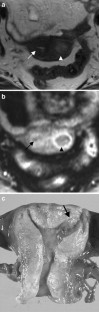

The endometrial cavity may demonstrate various imaging manifestations such as normal, reactive, inflammatory, and benign and malignant neoplasms. We evaluated usual and unusual magnetic resonance imaging (MRI) findings of the uterine endometrial cavity, and described the diagnostic clues to differential diagnoses. Surgically proven pathologies of the uterine endometrial cavity were evaluated retrospectively with pathologic correlation. The pathologies included benign endometrial neoplasms such as endometrial hyperplasia and polyp, malignant endometrial neoplasms such as endometrial carcinoma and carcinosarcoma, endometrial–myometrial neoplasm such as endometrial stromal sarcoma, pregnancy-related lesions in the endometrial cavity such as gestational trophoblastic diseases (hydatidiform mole, invasive mole and choriocarcinoma) and placental polyp, myometrial lesions simulating endometrial lesions such as submucosal leiomyoma and some adenomyosis, endometrial neoplasms simulating myometrial lesions such as adenomyomatous polyp and endometrial lesions arising in the hemicavity of a septate/bicornate uterus, and fluid collections in the uterine cavity (hydro/hemato/pyometra). It is important to recognize various imaging findings in these diseases, in order to make a correct preoperative diagnosis.

Fig. 4